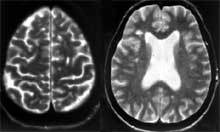

На МР-томограмах головного мозку у 91,8% хворих з РРС в стадії ремісії виявлялися одночасно не тільки осередки зниження інтенсивності сигналу в Т-1W режимі, але і осередки підвищення інтенсивності сигналу в Т-2W режимі, які зберігалися роками (Рис. 1а ). При загостренні РС мало місце певне збільшення вогнищ зниження інтенсивності сигналу в Т-1W режимі з формуванням зон перифокального набряку навколо них (Рис. 1б). Однак на підставі цих даних важко було судити про рівень активності демієлінізуючих процесу.

Мал. 1а, б. Вогнища демієлінізації в півкулях (а, зліва) і стовбурі (б, справа) головного мозку з підвищенням і зниженням інтенсивності сигналу при РРС.